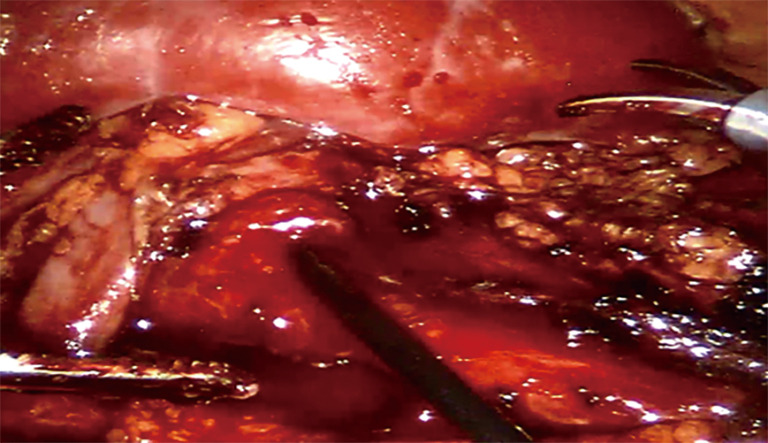

Methods: We conducted a retrospective study of pediatric patients with UPJO and renal calculi treated between March 2018 and June 2023. All patients underwent either RALP or conventional LP combined with flexible ureteroscopy. Preoperative imaging and standardized postoperative follow-up were used to assess surgical outcomes.